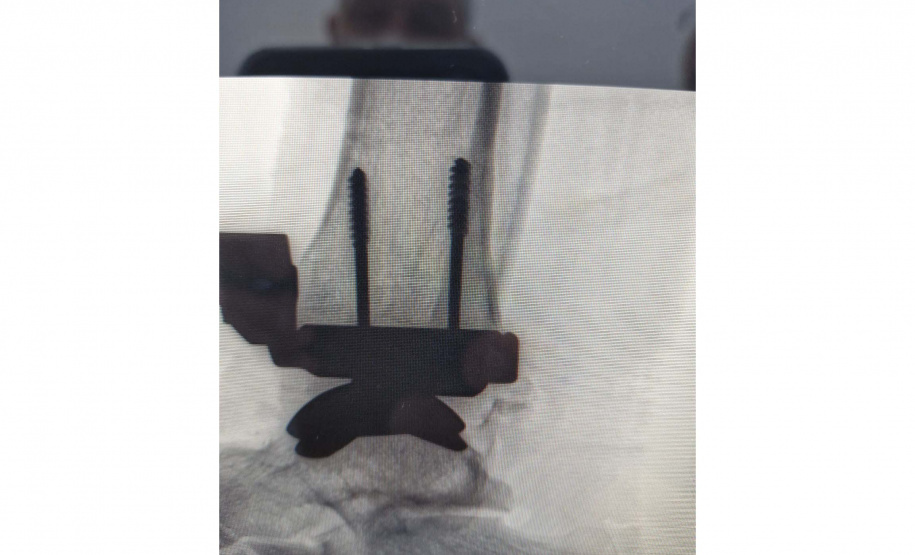

A cirurgia durou cerca de três horas com a equipe do médico Bruno Arnaldo Bonacin Moura. É considerada bastante complicada, pois requer treinamento altamente especializado para cortes ósseos, alinhamento dos componentes da prótese e equilíbrio do tornozelo. “Qualquer desvio milimétrico pode comprometer o resultado”, ponderou o médico.

DOR CONSTANTE – O paciente operado pela equipe é Heitor de Oliveira Tedesco. Ele foi vítima de um acidente de trabalho em 2022 e teve fratura exposta no tornozelo, o que obrigou uma cirurgia de emergência, com a colocação de seis pinos e uma placa.

Em fevereiro deste ano, o médico que o atendia optou por tirar os pinos e a placa e fez o pedido de uma nova cirurgia, quando apareceu a opção por uma prótese. Após a cirurgia, ele vem apresentando recuperação dentro do esperado pelos médicos, com melhora na movimentação, sem dor significativa e conseguindo retomar suas atividades de forma segura.